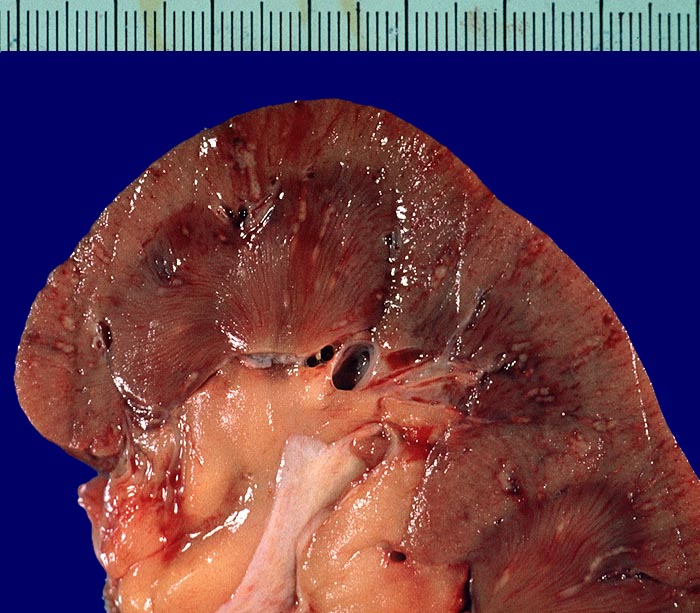

PathoPic ID 2941 - Septikopyämische Herde

Septikopyämische Herde

Entzündung infektiös

Niere

Niere, Harnwege

Zahlreiche in Mark und Rinde gelegene, wenige Millimeter grosse

gelbe Eiterherde umgeben von einem hämorrhagischen roten Randsaum.

Endokarditis

Makroskopie